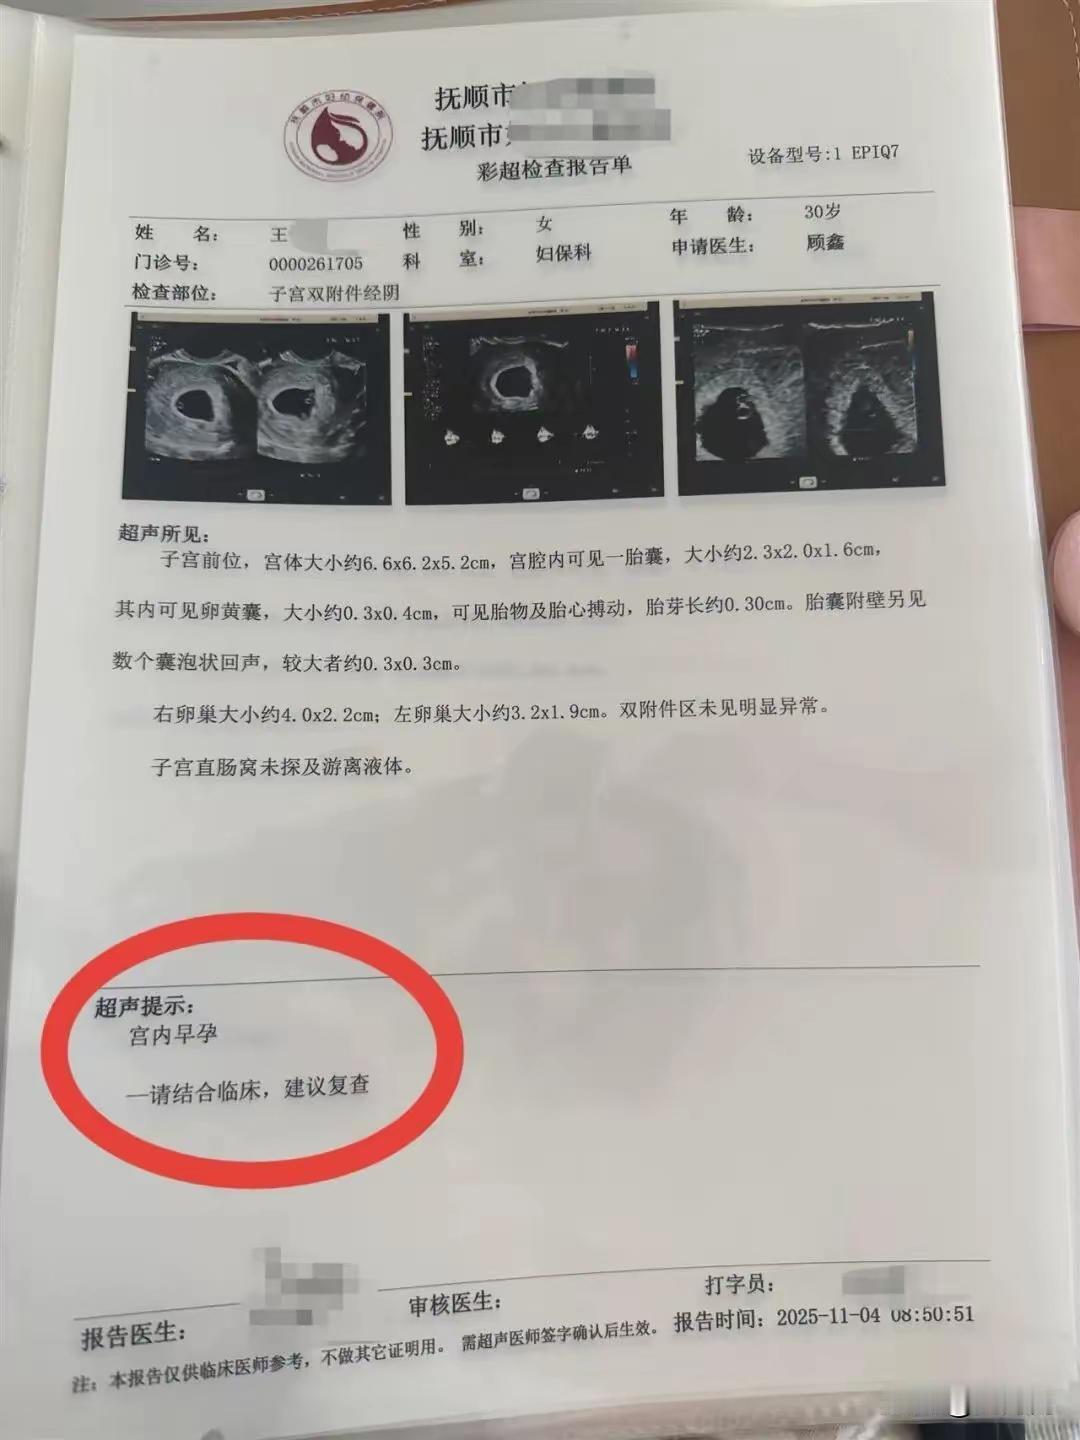

辽宁抚顺的一位准妈妈最近经历了人生中过山车般的时刻。怀孕16周的王女士,原本只是按部就班地进行产检,却在医院拿到了一份极其罕见的诊断报告。从去年11月到12月,短短一个月的时间里,她在医院进行了四次产检,每一次彩超单上的图像都在发生变化——最终确认,她怀上了四胞胎。 这并非普通的四胞胎。根据相关医生的诊断,王女士怀上的是同卵四胞胎。在医学领域,同卵四胞胎的发生率极低,属于非常罕见的个案。更复杂的情况在于,医生指出第四个胎儿为“无心畸胎”。这是一个专业性很强的术语,意味着这个胎儿虽然没有正常的心脏发育,但依然依赖其他胎儿的血液循环在母体内生存。这种特殊的医学状况,无疑给整个孕期增添了巨大的不确定性和风险。 对于普通家庭而言,多胞胎往往意味着双倍的喜悦,但在医学视角下,这更多代表着高风险妊娠。从数据来看,自然受孕情况下同卵四胞胎本就凤毛麟角,而伴随无心畸胎的情况更是让保胎之路布满荆棘。王女士在抚顺当地医院进行的这四次检查,实际上是一个不断排查和确认的过程。每一次彩超,不仅是在数胎儿的数量,更是在评估母体和每一个胎儿的生存质量。 网友们对此议论纷纷,有人感叹生命的奇妙与不易,也有人为即将到来的抚养压力感到担忧。毕竟,四个孩子的降生,对家庭的经济状况、父母的精力都是极大的考验。目前摆在王女士和家人面前的,不仅是喜悦,还有如何根据医生的专业建议,制定最科学、最安全的后续妊娠方案。 这起事件也给广大备孕及孕期女性提了个醒:规范的产检流程至关重要。像王女士这样,通过连续、定期的超声检查,才能及时发现多胎妊娠及胎儿发育异常等特殊情况。面对罕见病例,医学干预和监测是保障母婴安全的最有效手段。祝愿这位准妈妈能平安度过接下来的孕期,也希望这个小生命群体能在现代医学的保驾护航下,迎来最好的结局。 以上内容仅供参考和借鉴